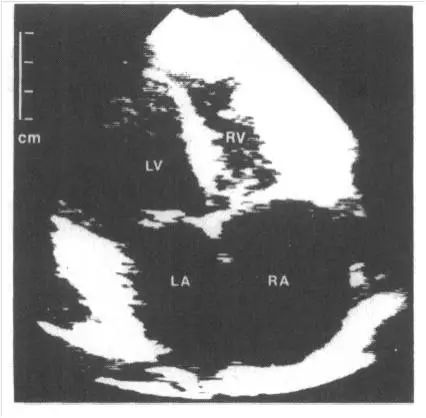

限制型心肌病ECHO:双房大;右室心尖部闭锁